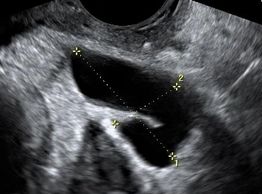

Hydrosalpinx may be confused for ovarian cysts or other conditions

A blocked fallopian tube can fill with fluid (hydrosalpinx), and then is predisposed to developing infection.

Blockage may be caused by endometriosis, prior infection, scarring, or unknown causes

Endometriosis may produce scarring and blockage of the fallopian tubes

Scarring with adhesions may block the fallopian tube. Adhesions may result from prior surgery, infection, or endometriosis.